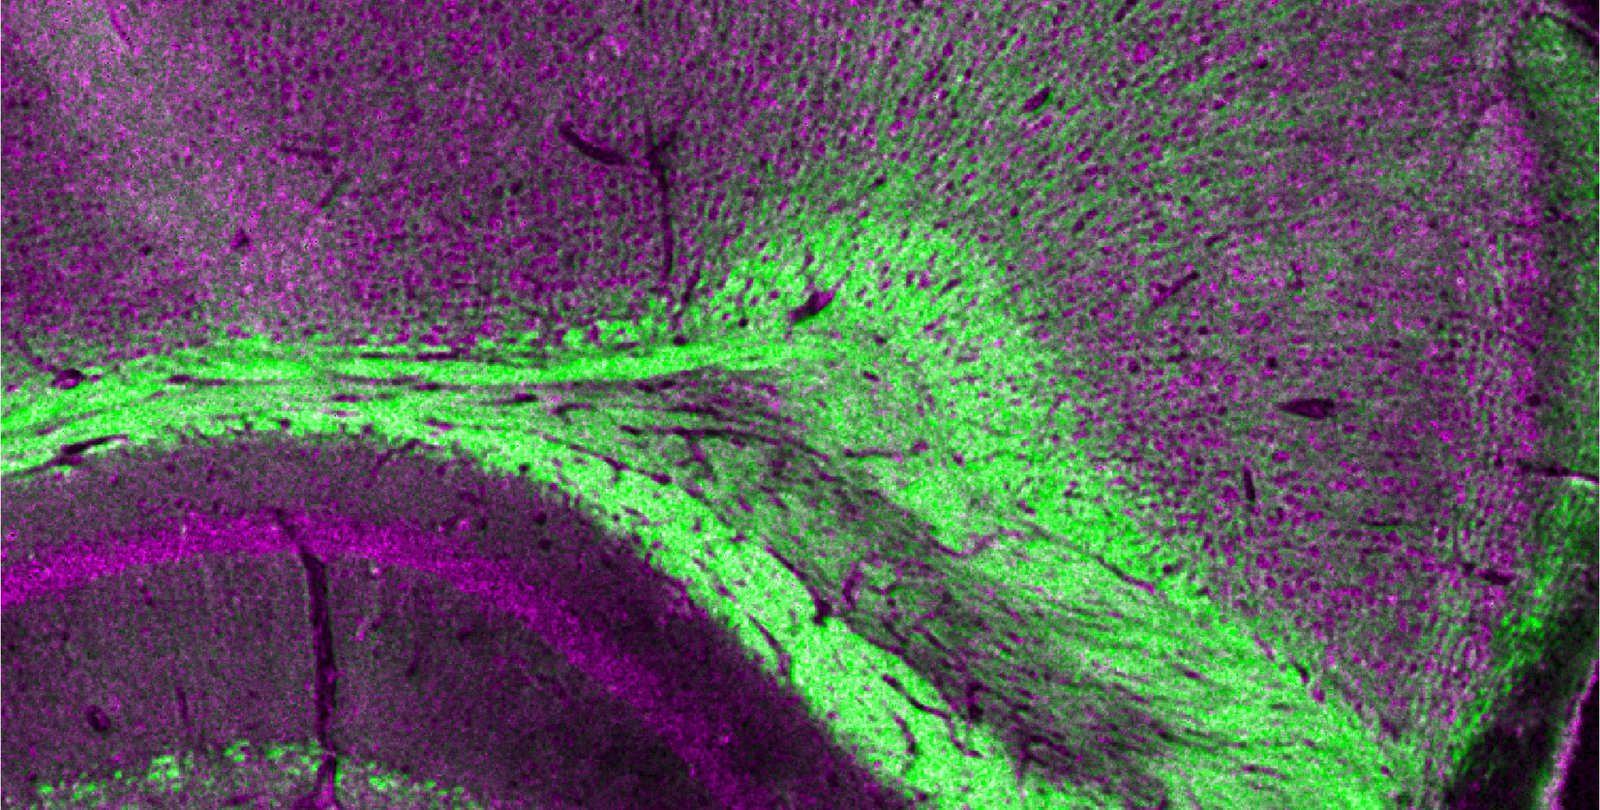

A region of a mouse imaged by the dual-laser microscopy technique. It is a purple and green cross section of tissue.

Researchers in Lihong Wang's lab have developed a new imaging technique that uses pulses from two kinds of lasers to take pictures of microscopic biological structures.